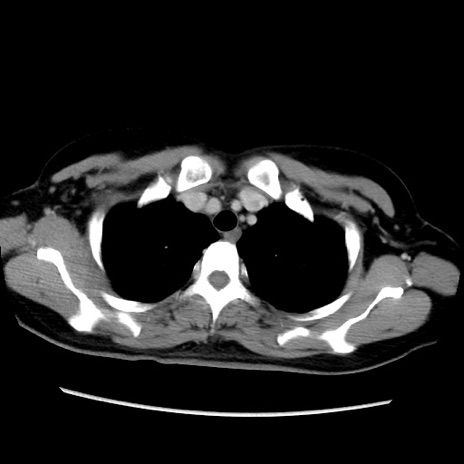

症例39(横断像)

【症例】40歳代女性

【主訴】上下腹部痛

【現病歴】2日目から下腹部痛あり。夜間は痛みで眠れなかった。昨日より上腹部痛と下痢が出現。臥位で痛みは軽快したため、休んでいた。本日になって臥位でも立位でも痛みが強くなってきたため救急要請。

【既往歴】子宮内膜症

【身体所見】部:平坦・軟、左上下腹部に圧痛あり、反跳痛あり。

【データ】WBC 21800、CRP 26.78